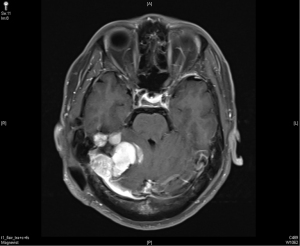

In April 2015, the patient took another course of radiotherapy as fractionated schedule of 5,940 cGy in 33 fractions, with 180 cGy in one fraction per day, 5 days a week, due to recurrence again nearby the previous tumor bed (Figure 3). The treatment volume of radiotherapy included the gross recurrent tumor with perifocal edematous change. This time, the recurrent tumor was under control and stable for about one and half year (Figure 4).

In December 2016, his brain MRI showed size increase of the previous recurrent tumor, and the patient received the third course of radiotherapy with a cumulative dose as 6,000 cGy in 30 fractions. No more enlargement of tumor was noted in the next 3 years.